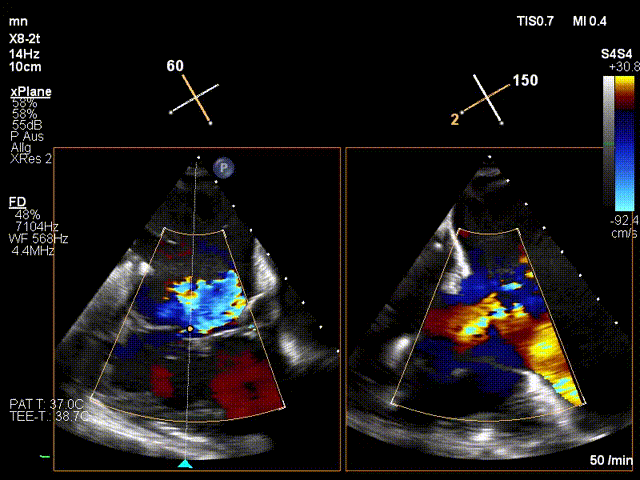

术后人工三尖瓣膜工作良好

LuX-Valve Plus经血管三尖瓣置换系统本次“出海”圆满完成,术后Jörg Hausleiter教授对LuX-Valve Plus经血管三尖瓣置换系统的器械性能和治疗效果大为称赞,认为LuX-Valve Plus的手术体验非常好。术后即刻超声显示三尖瓣反流消失,血流动力学改善显著,患者恢复快。Anson Cheung教授也肯定了LuX-Valve Plus术中操作的便捷性,认为LuX-Valve Plus容错率高,对术中影像的依赖较小,后期希望可以更多的应用LuX-Valve Plus三尖瓣置换系统于临床实践,让更多的三尖瓣重度反流患者尽早获益,改善预后。